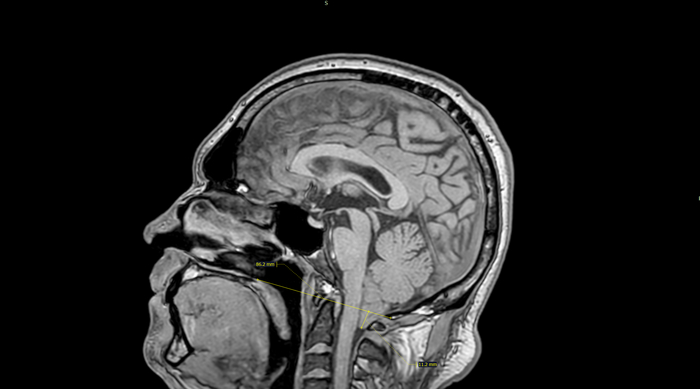

В больнице Оле провели КТ, которое подтвердило подозрения врачей скорой помощи. В срочном порядке девочку забрали на операцию по удалению внутримозговой гематомы правой теменной доли.

Во время операции выяснилось: у Оли врожденная аномалия сосудов — артериовенозная мальформация. Именно она стала причиной катастрофы. После операции девочка провела три дня в коме, а после — две с половиной недели в реанимации.